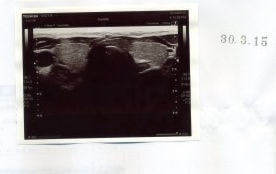

平成29年8月25日のエコーで甲状腺右葉に直径8mmの腫瘍を確認。4ヶ月後の12月14日にも確実に存在を確認していたのですが、何と7ヶ月後平成30年3月15日には消滅してしまいました。

何かの間違いかと、甲状腺内部をくまなく探しましたが、やはり見当たりません。腫瘍マーカーのCEA(基準値5.0)も平成29年8月「CEA6.3」→12月「CEA3.7」→平成30年3月「CEA3.3」と、とっくに正常値になっていて、さらに低値になっています。